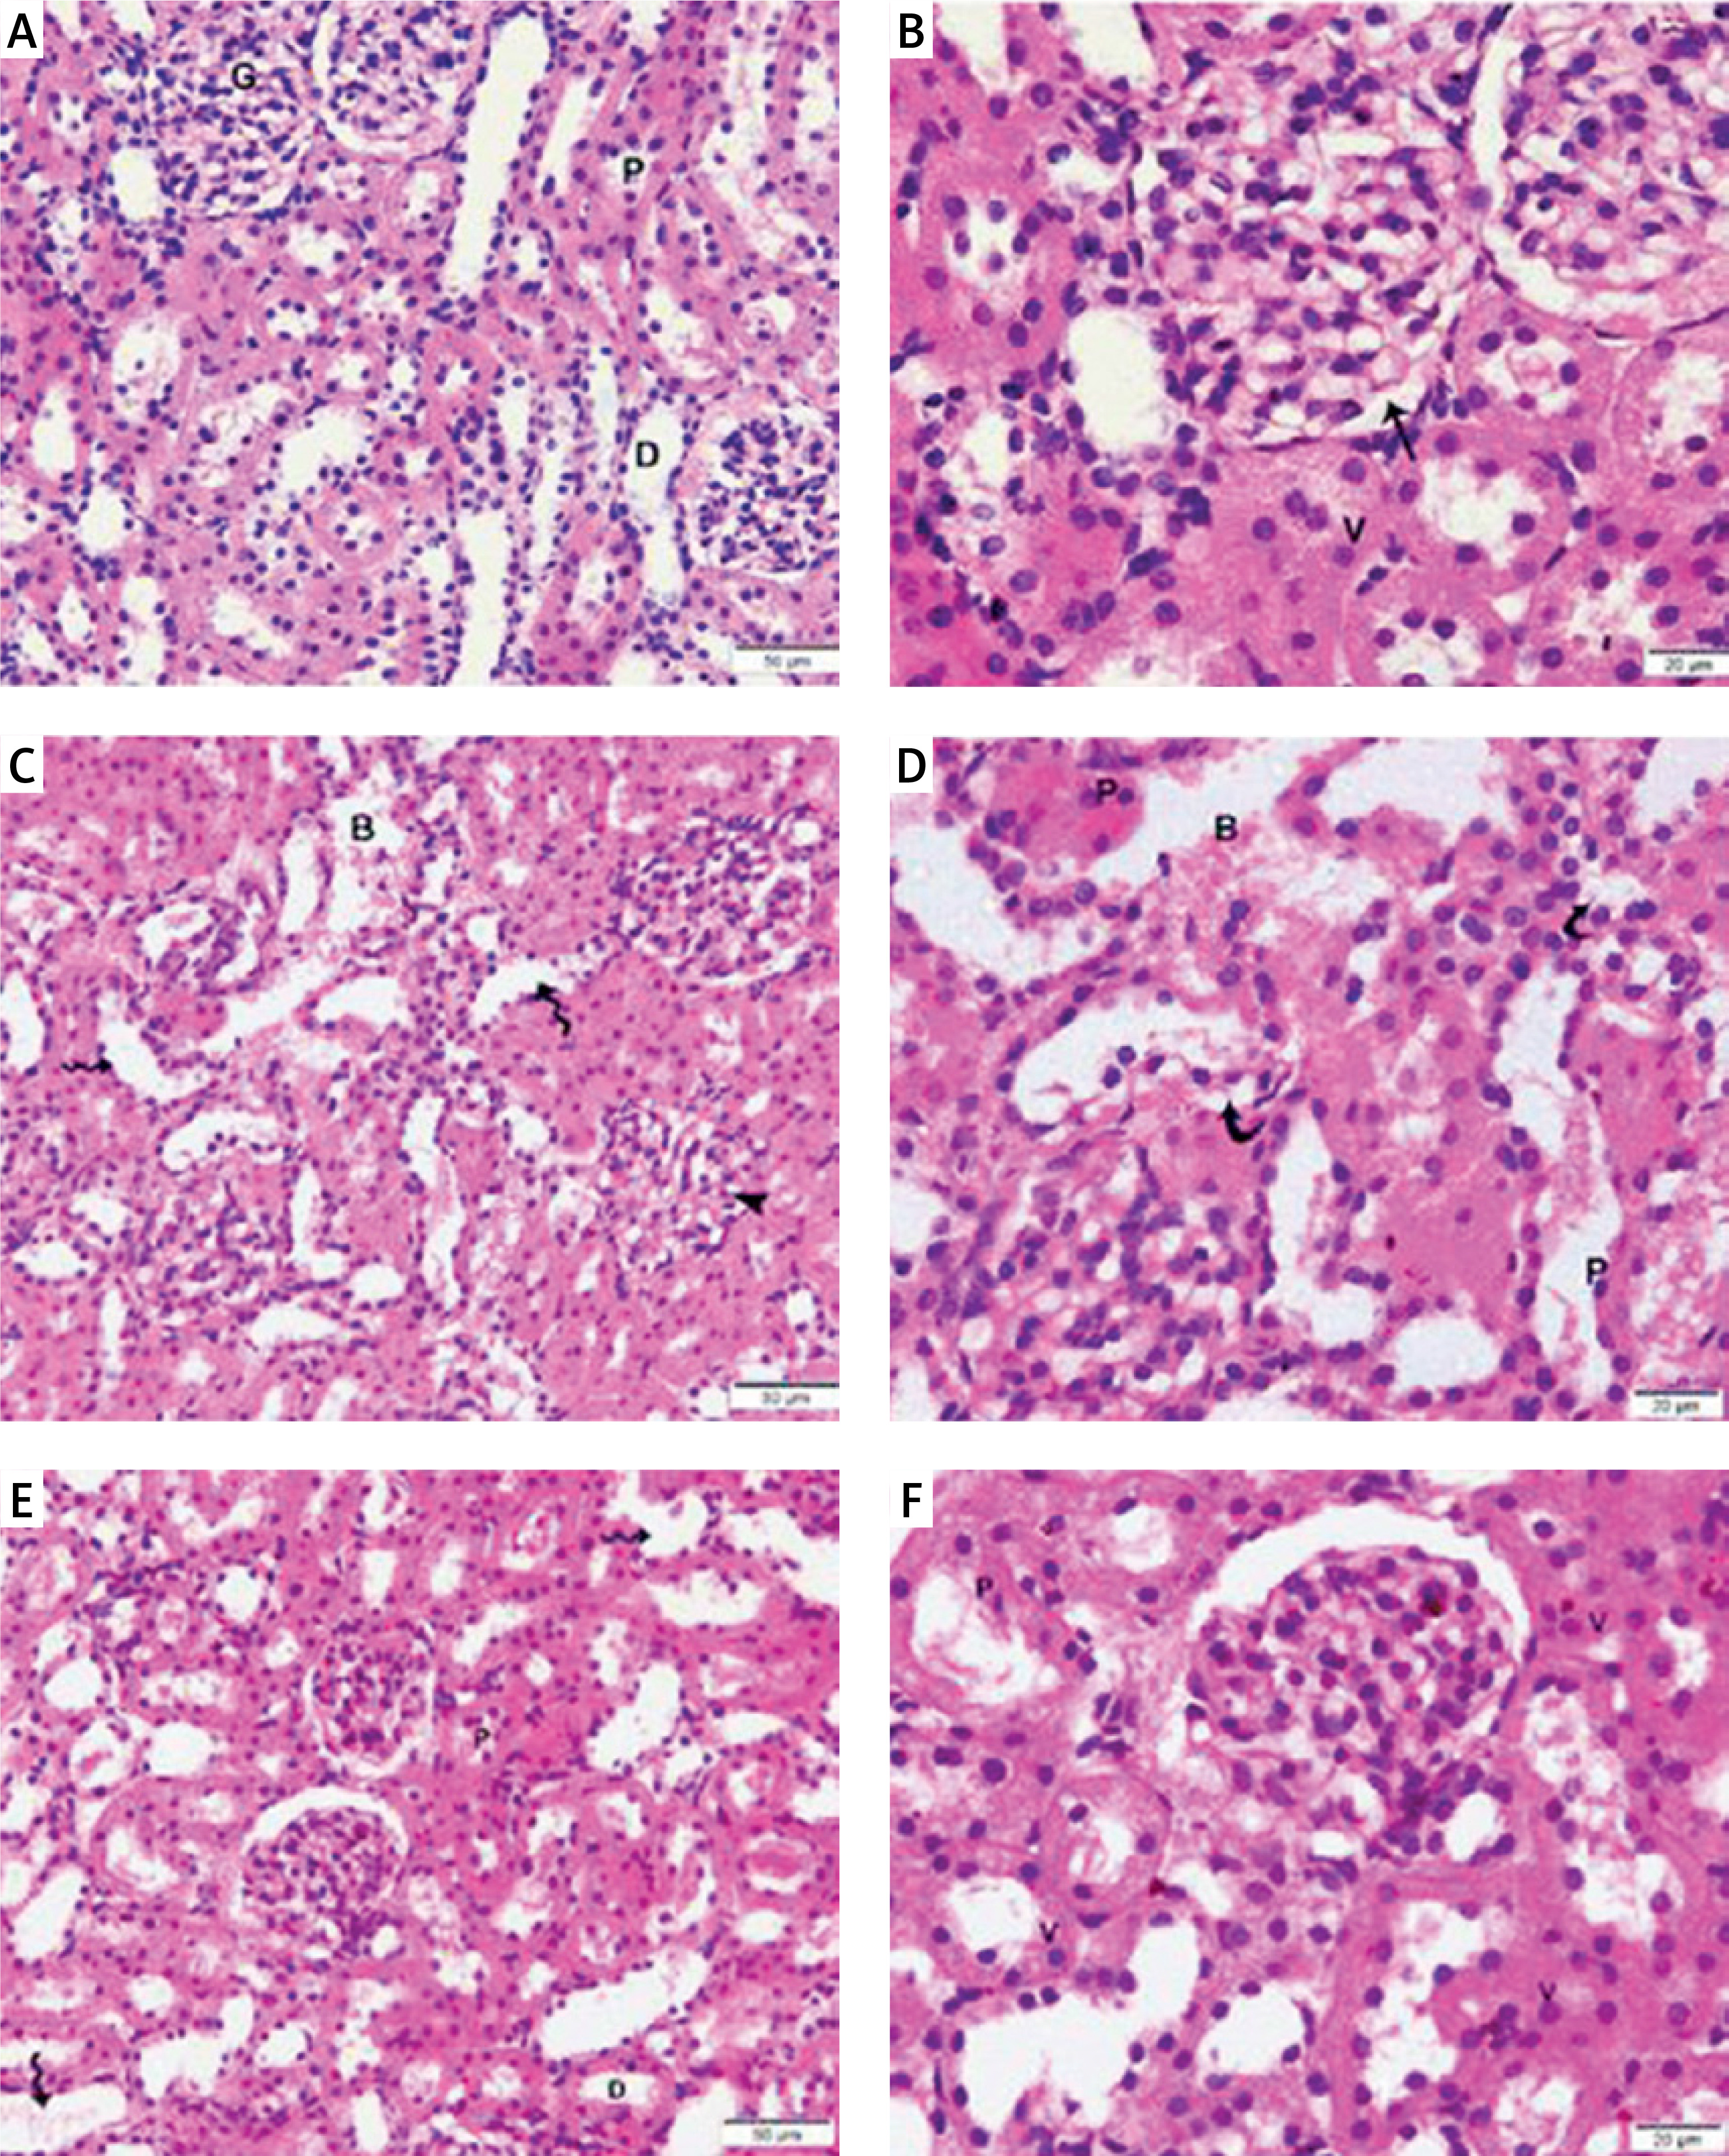

MSCs protected against diabetes-induced kidney injury and fibrosis

Diabetic nephropathy is marked by increased glomerular basement membrane thickness and mesangial matrix expansion, which eventually results in end-stage renal disease and renal fibrosis [35]. Therefore, we assessed all rat groups’ kidney injury and fibrosis levels (Figures 5–7). After staining with H&E (Figures 5 A–F), Masson (Figures 6 A–D), and α-SMA (Figures 7 A–D) stains, kidney sections were examined by light microscopy.

Figure 5

Photomicrographs of H&E-stained sections of the renal cortex. (A, B) Proximal (P) and distal (D) convoluted tubules bordered with cuboidal cells displaying vesicular nuclei (v) and acidophilic cytoplasm; Malpighian renal corpuscle with glomerulus (G); and narrow Bowman’s space (arrow) can be seen in the control group. (A, D) Diabetic group: dilated convoluted tubules (wavy arrow), dilated blood vessels (B), and deformed renal corpuscles (arrowhead). Vacuolated cytoplasm (curved arrow) and tiny, darkly-stained nuclei (P) are visible in the tubular epithelial cells. (F, E) The T2DM+MSCs group shows proximal (P) and distal (D) convoluted tubules bordered with cuboidal cells that display vesicular (v) and acidophilic cytoplasm, but some cells also have pyknotic nuclei (P). A few dilated convoluted tubules are visible (wavy arrow). (A, D, F ×400; C, E, ×200) (50 μm and 20 μm scale bars)

Compared to standard kidney architecture (Figures 5 A, B), diabetes caused distorted renal corpuscles, dilated convoluted tubules, and dilated blood vessels. The tubular epithelial cells show small, darkly stained nuclei and vacuolated cytoplasm (Figures 5 C, D). Masson-stained regions (Figure 6 B) revealed coarse collagen build-up in the renal interstitium among the tubules and around blood vessels. Additionally, α-SMA immunostained sections in the diabetic group showed strong, widespread positive α-SMA immunostaining cells in the wall of the blood vessels and the renal interstitium (Figure 6 B).

MSC treatment initially mitigated diabetic nephropathy (Figures 5 E, F). This is evidenced by the quantification of collagen deposition in the renal interstitium of sections stained with Masson stain (Figure 6 C), which demonstrated effective (p < 0.0001) inhibition of collagen build-up by MSCs to levels comparable to the control group. Also, MSC administration showed minimal positive α-SMA immunostaining in the wall of the blood vessels and in the renal interstitium, which indicates the reduction of interstitial α-SMA positive cells that are engaged in the development of interstitial fibrosis (Figures 7 A–D) [36]. Morphometry showed that MSCs decreased collagen deposition by reducing the Masson trichome staining and the α-SMA immunostaining area %.